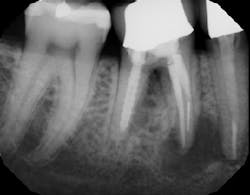

The best method of preventing nerve injury is to be prepared and evaluate nerve anatomy prior to the procedure on panoramic radiography and CT scans. (4) Several techniques have been described to reduce the risk of nerve injury during tooth extraction when the tooth-nerve is in proximity. Orthodontic extrusion, (5) surgical sectioning, (6) and induced spontaneous eruption (7) are all well covered in the literature. However, there seems to be a lack of discussion in the literature regarding the incidence of iatrogenic nerve injury due to socket debridement post tooth extraction.

In summation, the best treatment for nerve injury continues to be prevention. If there is any doubt by the treating clinician as to the proximity of an odontogenic lesion to the nerve space (figure 4), a CT scan prior to extraction therapy is the gold standard of care (figure 5). This pretreatment diagnostic can avoid both clinical and legal headaches.

Figure 4: Another case demonstrating periapical pathology and its proximity to the IAN